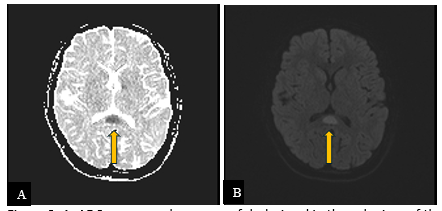

Diffusion-weighted imaging revealed bright signal with corresponding dark signal on ADC map, consistent with restricted diffusion (Figure 3). The rest of the brain was normal.

Figure 3: A. ADC map reveals an area of dark signal in the splenium of the corpus callosum (arrow). B. On diffusion-weighted imaging (DWI), there is corresponding bright signal (arrow). Imaging features are consistent with restricted diffusion.